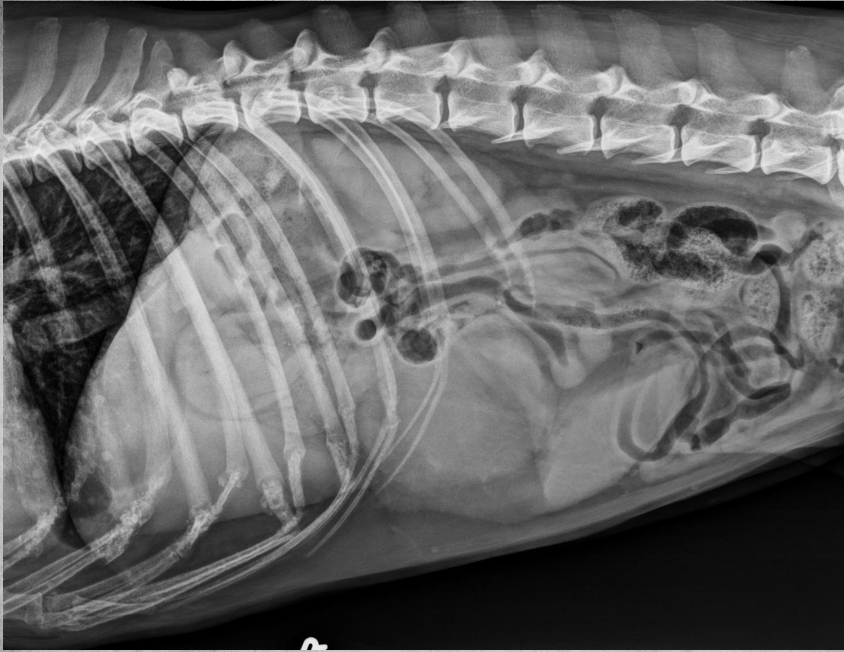

●10 yo female sterilized rottweiler

●Vomiting after every meal for 2 days

● Soft tissue opacity in the area of stomach

● Metal staple in colon

● Metal implant in one knee (from

previous surgery)

● Soft foreign body in stomach – grass,

fabric, wrapping paper

major organs in abdo cavity are hazy and poorly viewed, and lumen of stomach not viewable due to fabric foreign body in stomach.

cecum visible on VD, gas filled bubbles.